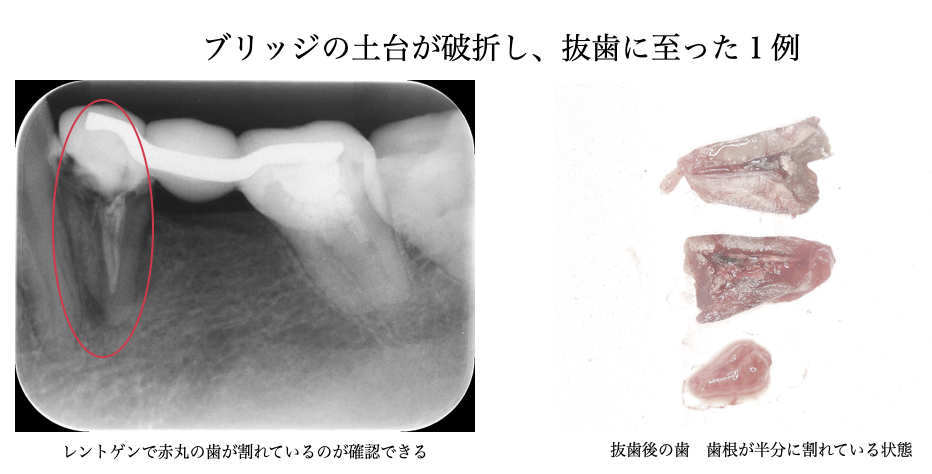

③歯の破折の場合

・両隣の歯(土台になる歯)を大きく削る必要がある

・土台となる歯は、歯が無い部分のダミーの歯にかかる力も負担する必要があるため、歯根破折や歯周

病の進行リスクが上がる

・被せ物のため、2次虫歯による再治療のリスクがある